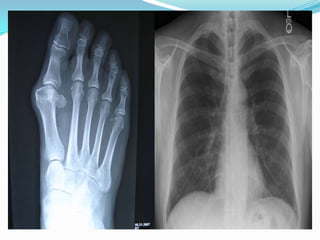

X-rays  X-rays arebasically electromagnetic radiations which are used to create images of inside your body.  The images show the parts of your body in different shades of black and white due to different level of absorption of x-rays by different tissues  Calcium in bones absorbs x-rays the most, so bones look white. Fat and other soft tissues absorb less, and look gray.  Air absorbs the least, so lungs look black.

 The mostfamiliar use of x-rays is checking for broken bones  However, x-rays are also used in other ways.  For example, chest x-rays can spot pneumonia.  Mammograms use x-rays to look for breast cancer.